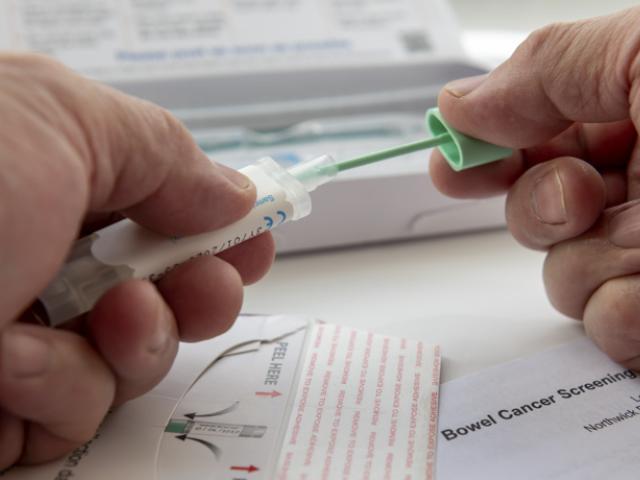

Detectar el cáncer de colon a tiempo es sumamente importante, sobre todo porque mejora el pronóstico de los pacientes que padecen esta enfermedad.